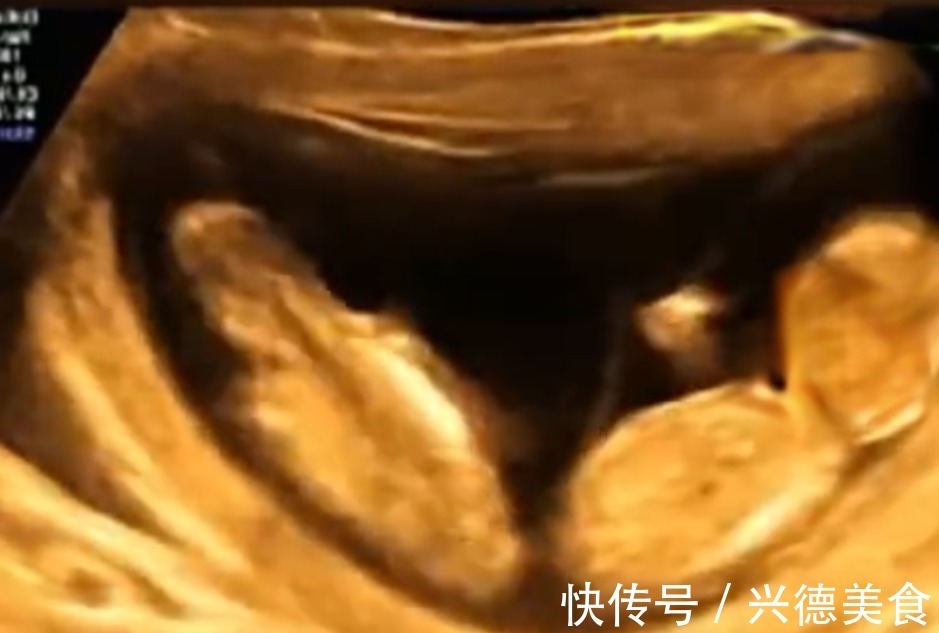

可能孩子在妈妈肚子里在汲取营养或是吮吸手指,这是常见的现象。但生活中也有十分罕见的,在河南有一位孕妈做四维彩超的时候突然开始腹痛,能感受到宝宝在肚子里的活动。做B超的时候发现两个宝宝正在闹着玩,在妈妈的肚子里打架。看到了这两个宝宝的未来一定是一个挨揍一个受欺负。网友们纷纷震惊评论说“看起来是单方面的在挨打。”“所以我下个月预产期,等他长大了我就找机会揍他一顿,不然不能泄愤。”“抢位置大作战。”